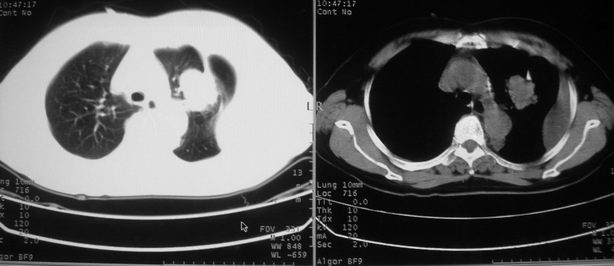

以下是引用w_jianhua在2008-5-22 12:59:00的发言:[br]1.左肺上叶肺癌并左侧胸腔积液可能性大。2不除外支气管内膜结核并包裹性胸腔积液,建议支气管镜检3.左肺下叶肺大泡,肺气肿